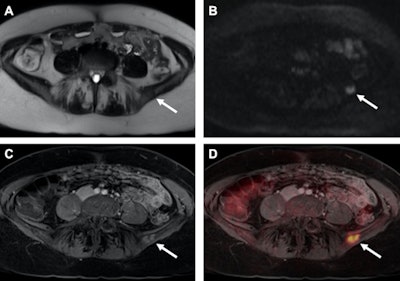

In addition, the scans revealed a total of 165 suspect lesions, of which there were 122 malignant tumors (74%) and and 43 benign lesions (26%). Among the 25 patients with breast cancer relapse, 18 patients (72%) experienced metastatic disease. The other seven patients (28%) suffered from unifocal cancer localizations, and a local breast cancer recurrence was found in five patients (20%).

Regarding lesion conspicuity and differentiating between malignant and benign lesions, contrast-enhanced T1-weighted VIBE imaging performed the best with significantly higher values compared with T2-weighted HASTE or DWI. T2-weighted HASTE also outperformed DWI in distinguishing benign lesions, while there was no statistically significant difference between the two MR sequences in differentiating malignant lesions (p > 0.05).